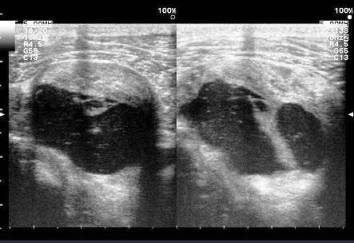

Ultrasonido de la rodilla donde se observa gran acumulo de líquido sinovial en bolsa sub cuadricipital, aumento de la celularidad del líquido, con imágenes de tabiques. Imagen 8

Imagen 8. Ultrasonido de la rodilla con acumulo de líquido sinovial